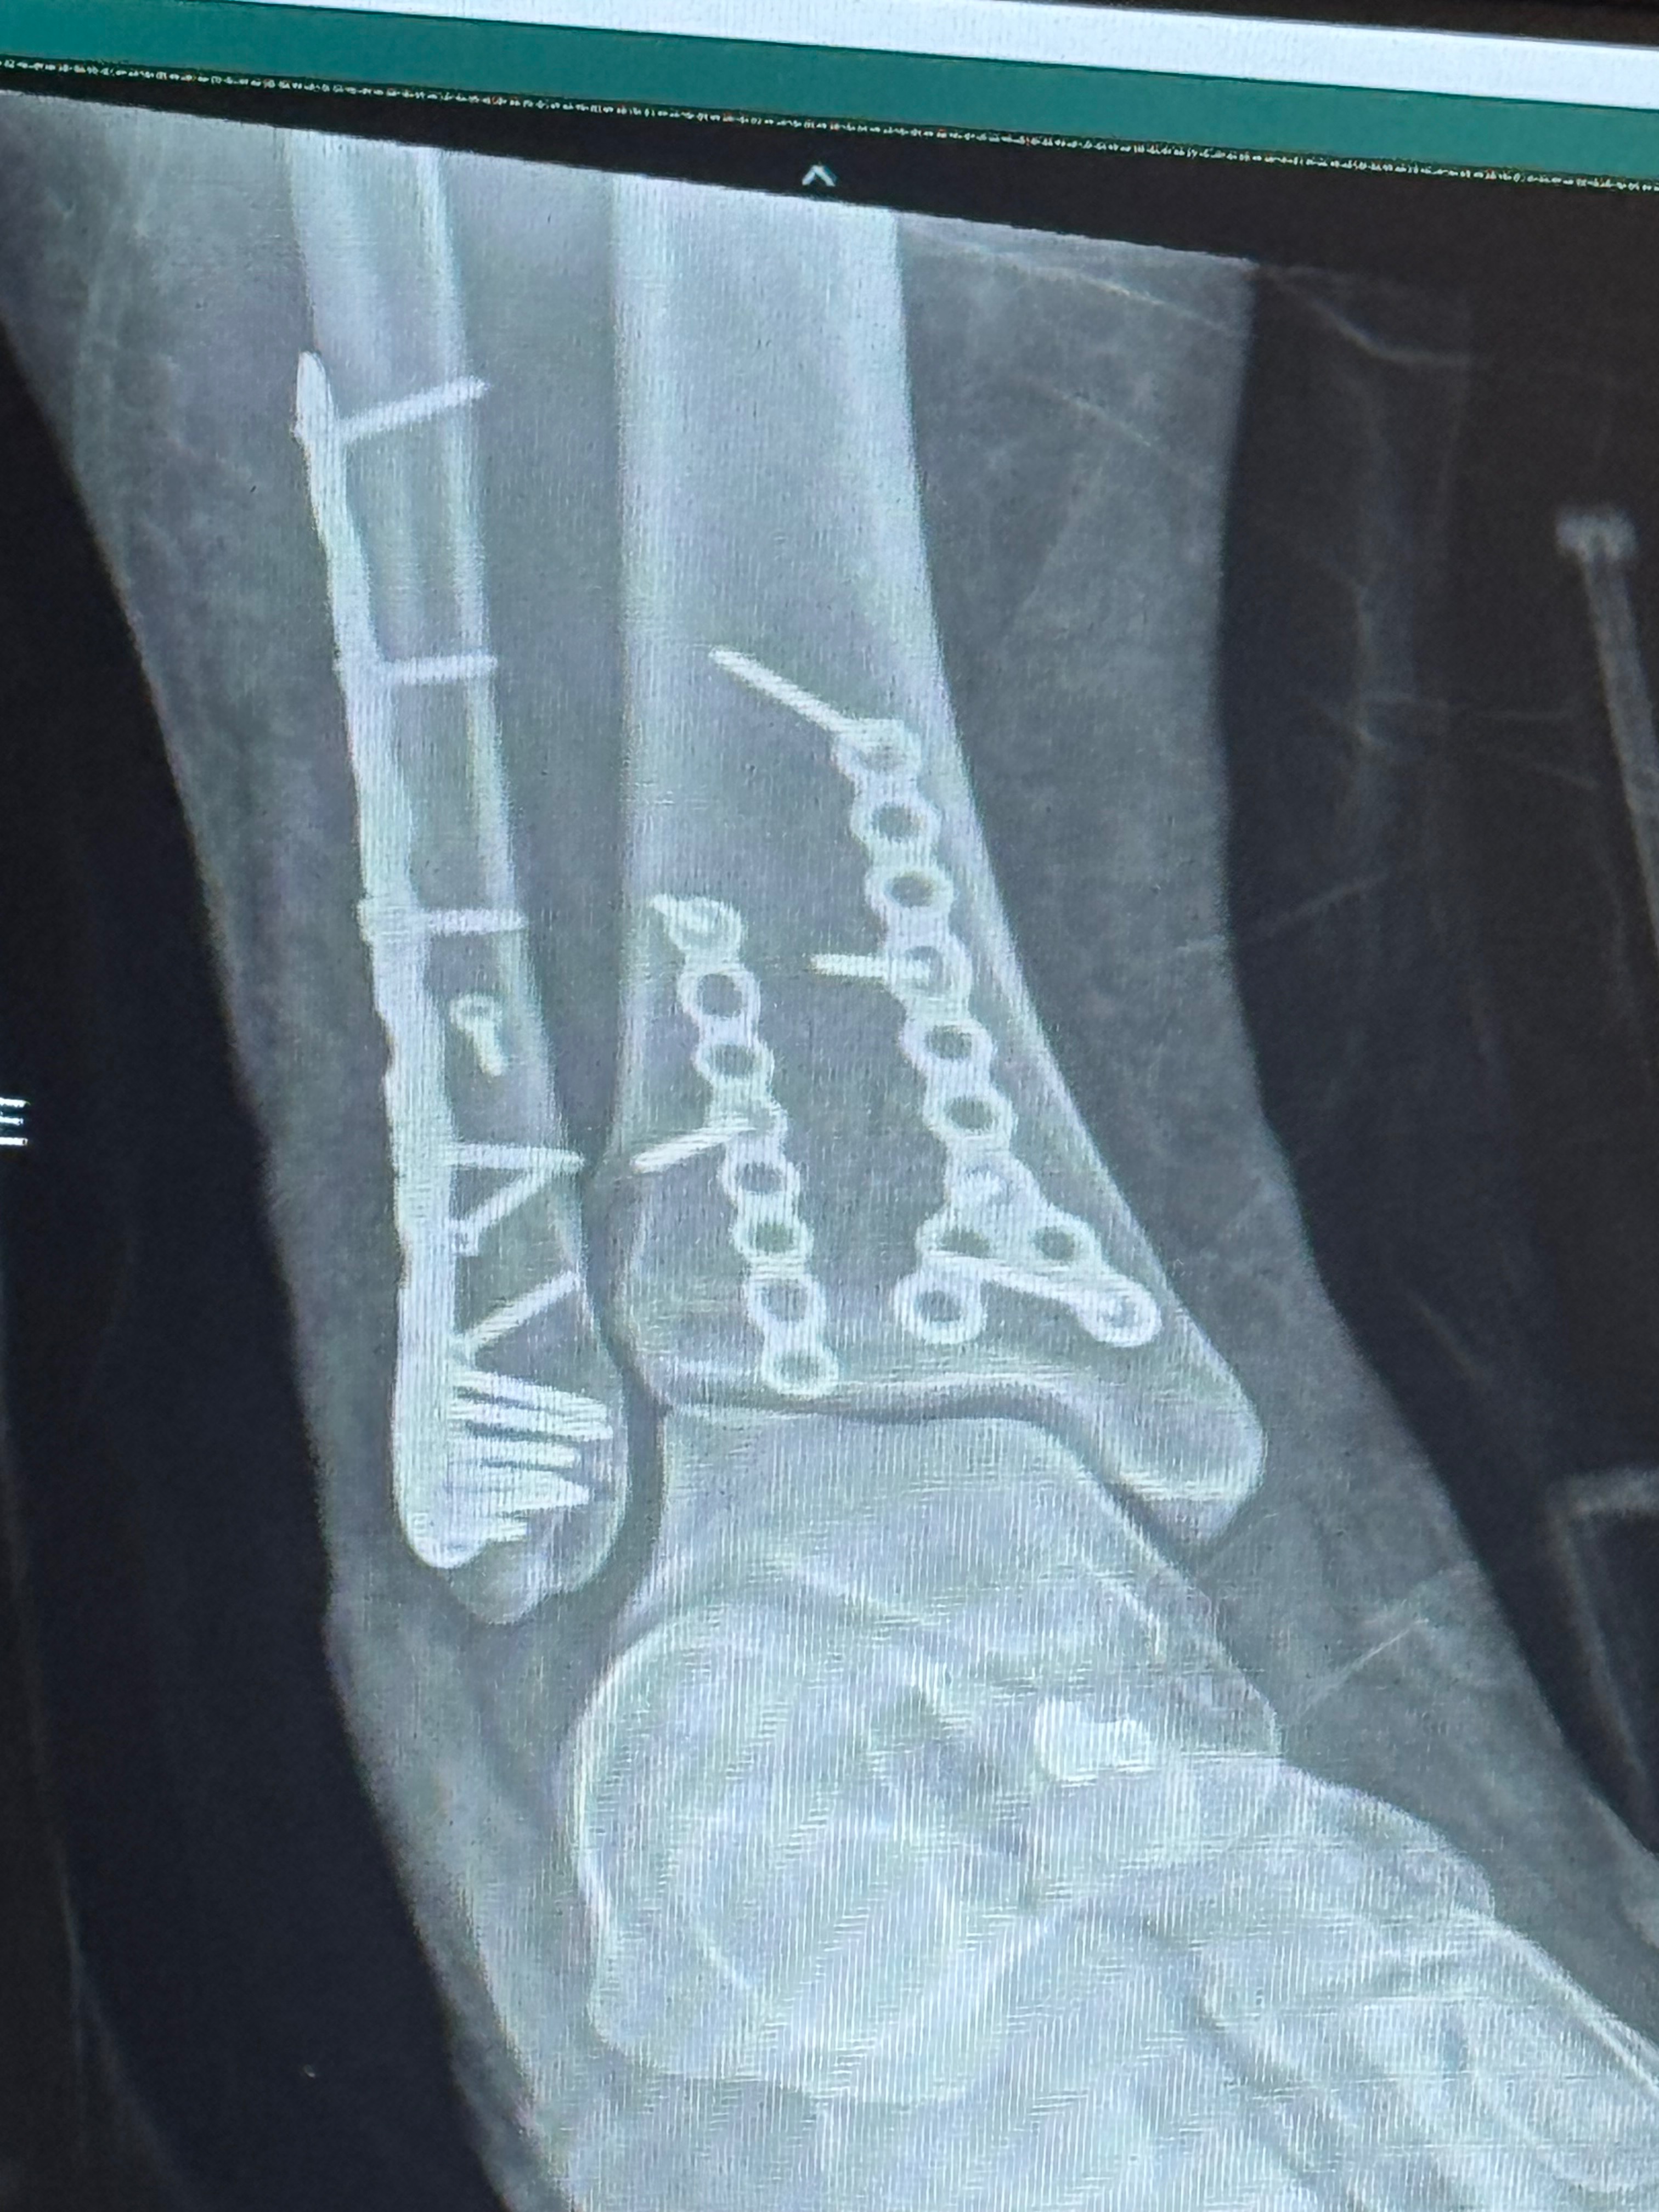

Hello we are the Garino’s, recently my husband broke his ankle quite severely which he had to take an ambulance to the hospital for as well as had to stay in patient while he had surgery to correct the bones. This has left us with a couple varying medical bills as unfortunately he does not have insurance due to a new job and he was also let go from his position due to him needing to be out of work for several months. I understand this is difficult times for everyone and I don’t expect anyone that cannot donate to do so but if you have the extra means and are willing, even a penny will help us immensely as we navigate only having one income source and paying for his medical and necessary appointments such as therapy. Thank you for taking the time to read this, have a great day.